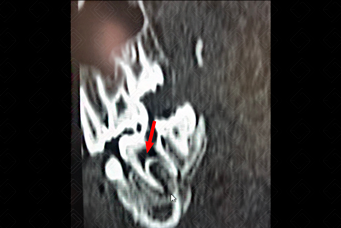

Texto alternativo para a imagem Créditos: Dra. Elazir Mota - Rio de Janeiro/RJ

Descrição da figura: Tomografia computadorizada de face direcionada para avaliação dentária, evidenciando extensa cárie no segundo molar inferior, acometendo o esmalte, a dentina e região pulpar (seta vermelha). Observe a área de hiperluscência junto da raiz do doente, traduzindo a presença de doença periapical (seta branca).

Doença periapical ou periodontite apical: R efere-se a um espectro de doenças que ocorre ao redor do ápice do dente, incluindo o granuloma periapical , cisto periapical e abscesso periapical . U sualmente, está associada ao processo de cárie dentária que, quando não tratada, evolui para doença periapical. [cms-watermark]